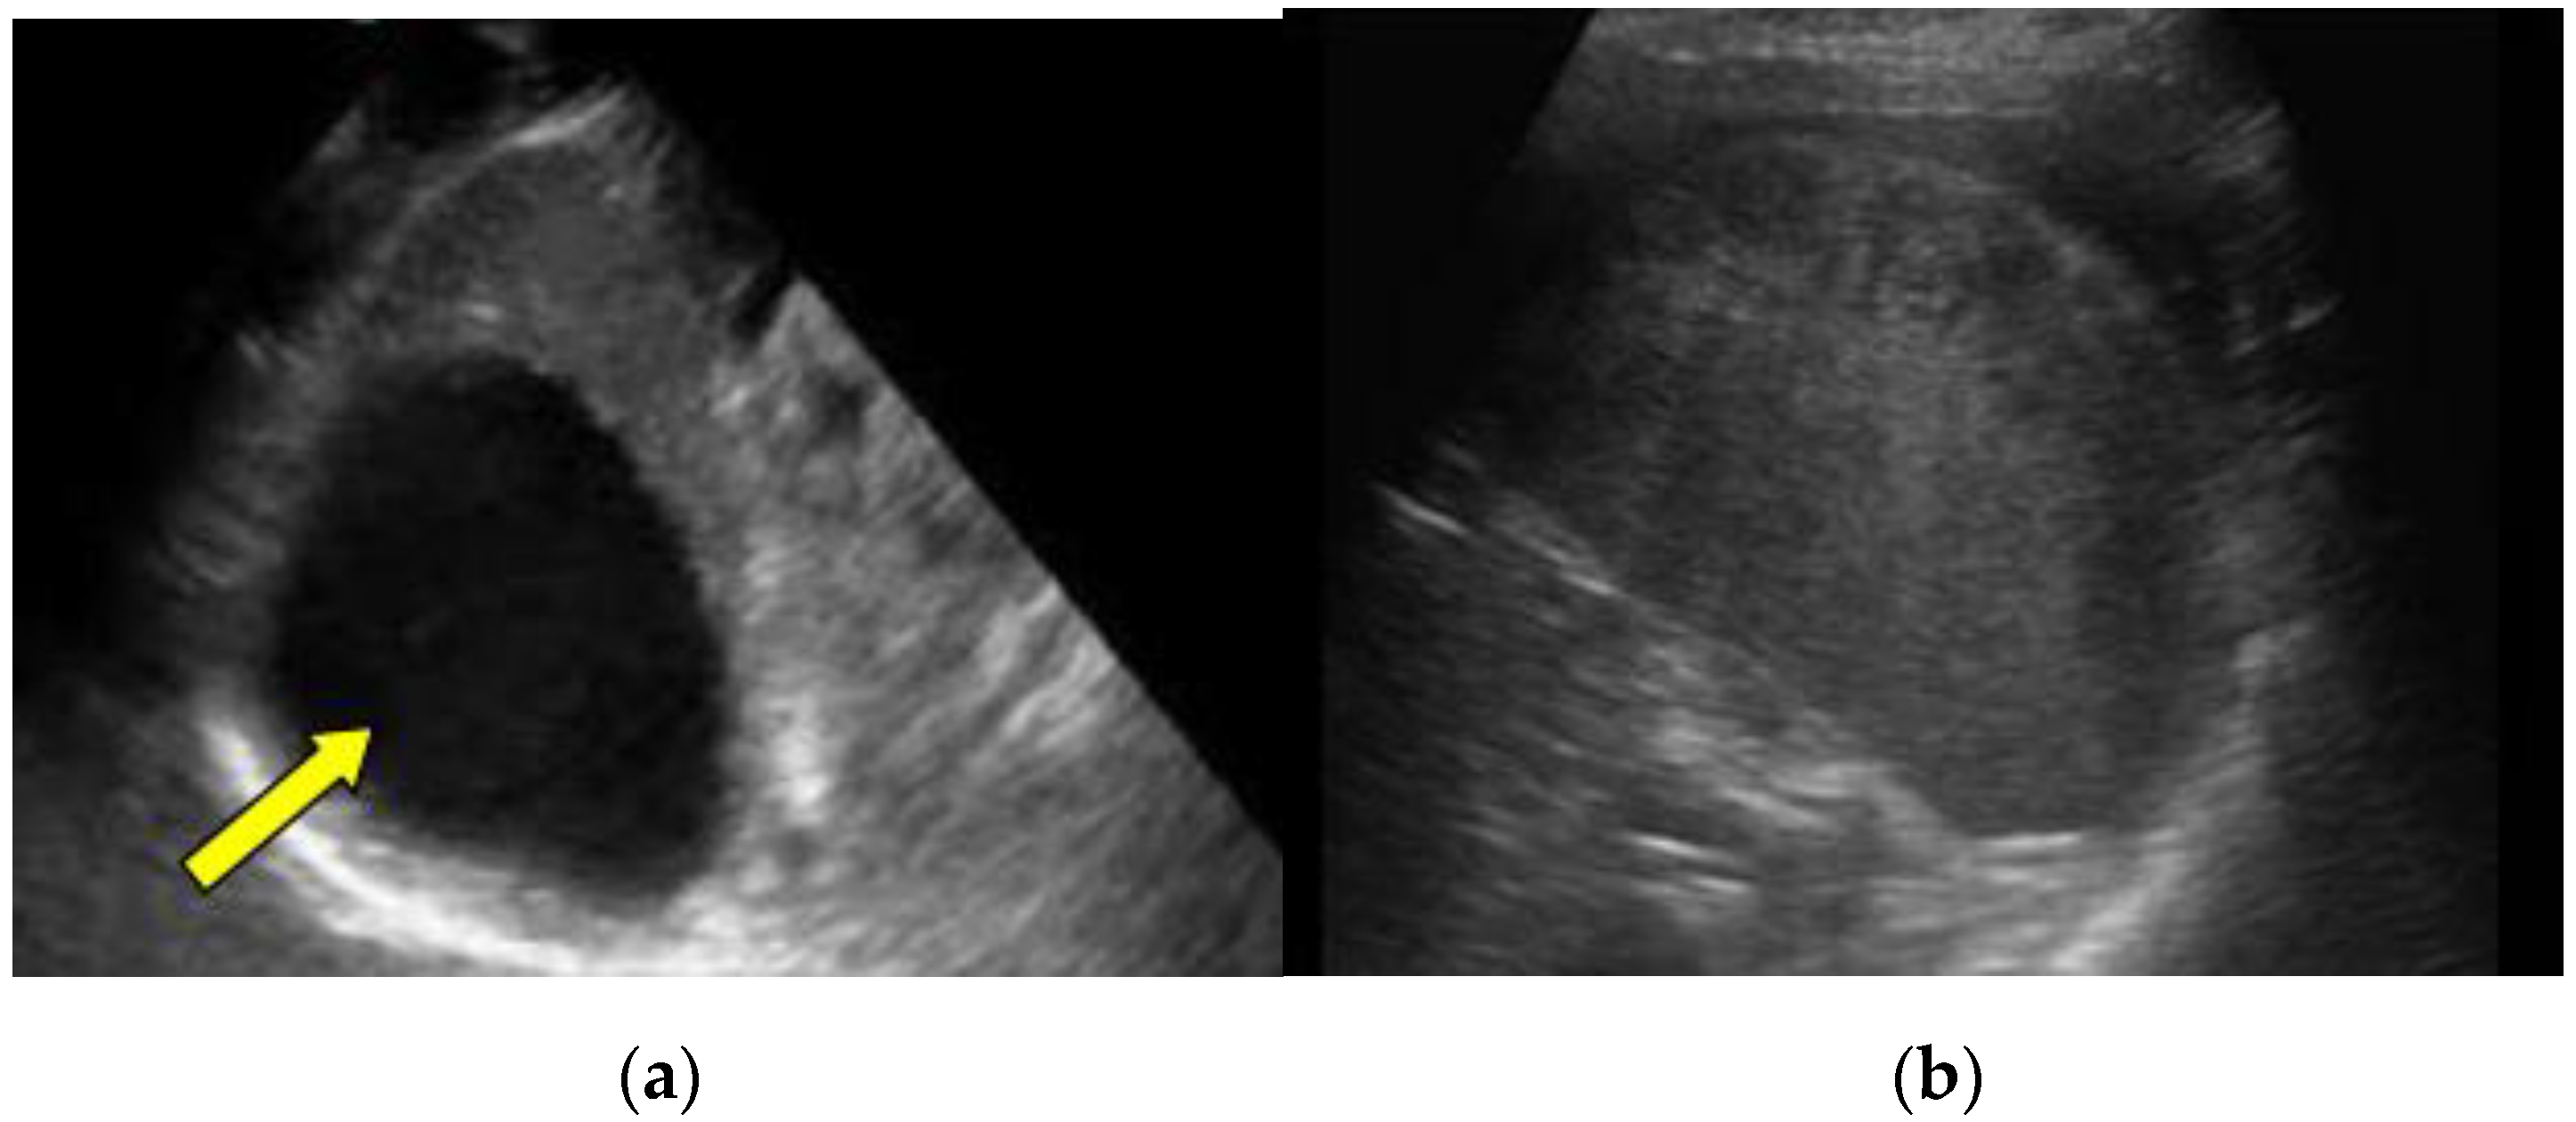

The complications were in direct correlation with the injury grade: seven were found in patients with grade IV injuries (9.21%), five were found in children with grade III injuries (6.57%), three were found in patients with grade II injuries (3.94%), and one was found in a patient with a grade I injury (1.31%). Figure 2 presents marginated hypoechoic pseudocyst after the grade IV splenic injury (2a) and subcapsular hematoma after the grade III splenic injury (2b).

Figure 2. (a) A follow-up ultrasound examination, three months after the grade IV splenic injury (patient No. 16 in Table 3). Oblique ultrasound scans diagnosed regularly marginated hypoechoic pseudocyst measuring 50 × 55 mm2 in size; (b) A transverse scans on a follow-up ultrasound examination, 30 days after trauma revealed subcapsular hematoma 52 × 23 mm2 in size. Patient had grade III splenic injury after a fall from a standing height (patient No. 3 in Table 3).